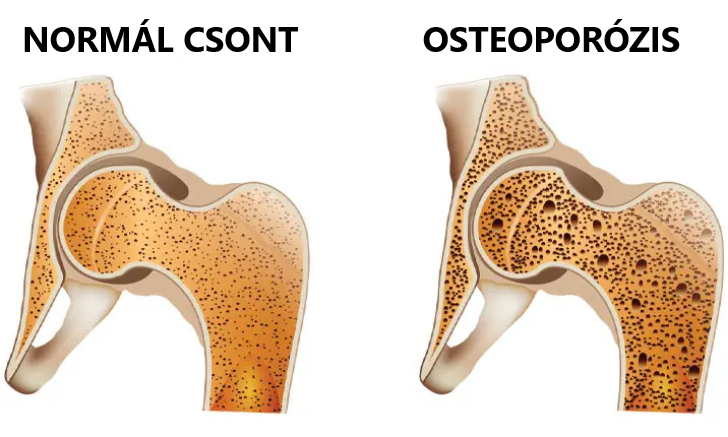

A csontritkulás olyan állapot, amelyben a csontok fokozatosan gyengülnek, ezért könnyebben eltörhetnek. Lassan alakul ki, és sokszor csak akkor derül ki, amikor már bekövetkezett egy törés. Bár az életkor, az öröklött hajlam és a hormonális változások erősen befolyásolják, a táplálkozás és a mindennapi szokások is sokat számítanak.

Ha ez az egyensúly felborul, például helytelen étrend vagy kedvezőtlen szokások miatt, a csontok idővel törékenyebbé válhatnak.